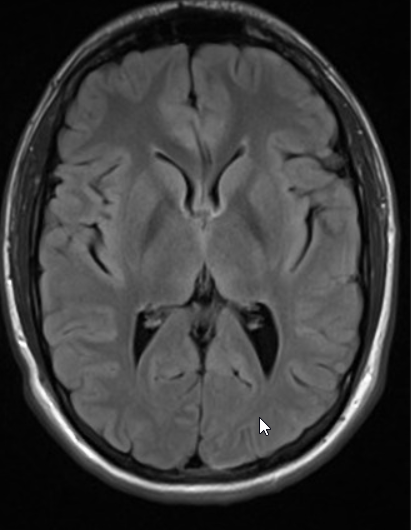

As you can see the image alongside of a brain. This specific brain has no tumor. Anyone can easily tells that this brain image is a free tumor. Now lets move towards the python code for creating neural network and training the CNN model on brain.